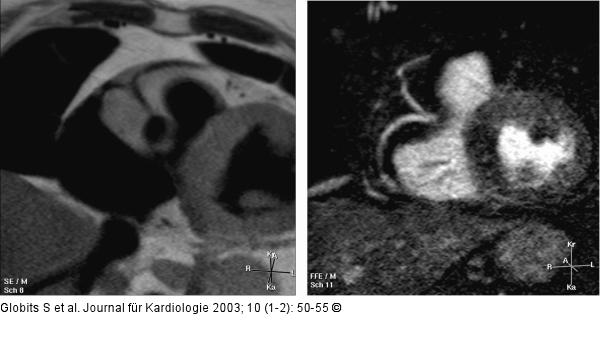

Abbildung 9: Kardiale Magnetresonanztomographie Koronargefäßanomalie mit Abgang der LCX aus der RCA. M2D-TSE (black blood) links, 3D-bTFE in Atemanhaltetechnik (bright blood) rechts |

Koronargefäßanomalie mit Abgang der LCX aus der RCA. M2D-TSE (black blood) links, 3D-bTFE in Atemanhaltetechnik (bright blood) rechts |